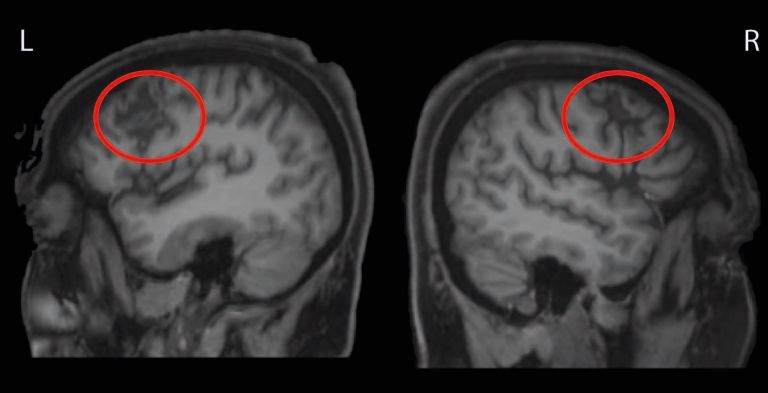

Spiegelt sich ADHS bei Kindern auch im Gehirn wider?

Sie können nicht ruhig sitzen bleiben, sich beherrschen oder über eine längere Zeit konzentrieren: Kinder mit der Aufmerksamkeitsdefizit-/Hyperaktivitätsstörung (ADHS). Kann man bei den Kleinen Auffälligkeiten im Gehirn finden?

11.04.2014